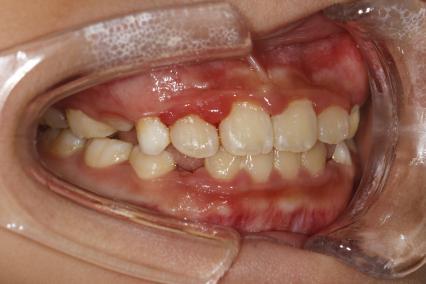

案例一:

治疗前

治疗后